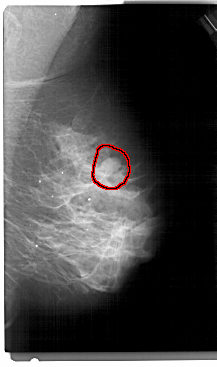

A_1305_1.RIGHT_CC

RIGHT_CC LINES 5386 PIXELS_PER_LINE 2851 BITS_PER_PIXEL 12 RESOLUTION 43.5 OVERLAY

FILE: A_1305_1.RIGHT_CC.OVERLAY

TOTAL_ABNORMALITIES 1

ABNORMALITY 1

LESION_TYPE MASS SHAPE OVAL MARGINS CIRCUMSCRIBED

ASSESSMENT 4

SUBTLETY 4

PATHOLOGY BENIGN

TOTAL_OUTLINES 1

BOUNDARY